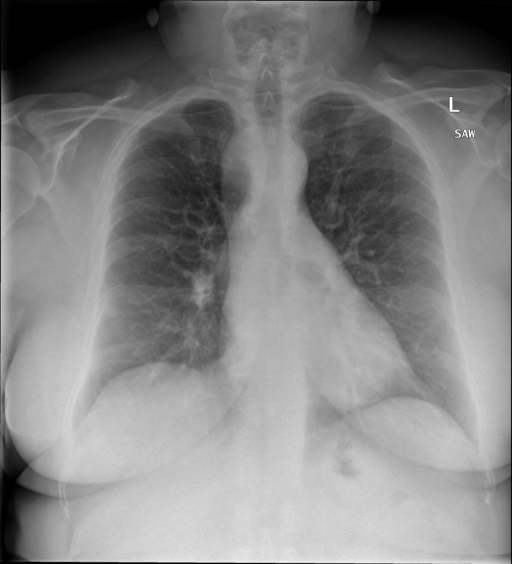

|X光影像|诊疗报告(医生)|XrayGLM|

|:-|:-|:-|

||心影形态在正常范围内。没有急性骨质异常。有可能出现没有明显的吸水或肺实质状况的线索。没有大面积积液或气胸。有可能怀疑其有误吸或肺实质问题。为了确诊和治疗,可能需要进行适当的影像学随访。|心脏大小正常,肺部和纵隔轮廓清晰。没有急性异常或活动受限的证据。没有任何明显的气胸、胸腔积液或肺不张的迹象。此外,也没有发现任何局灶性骨质异常或其他急性疾病。|